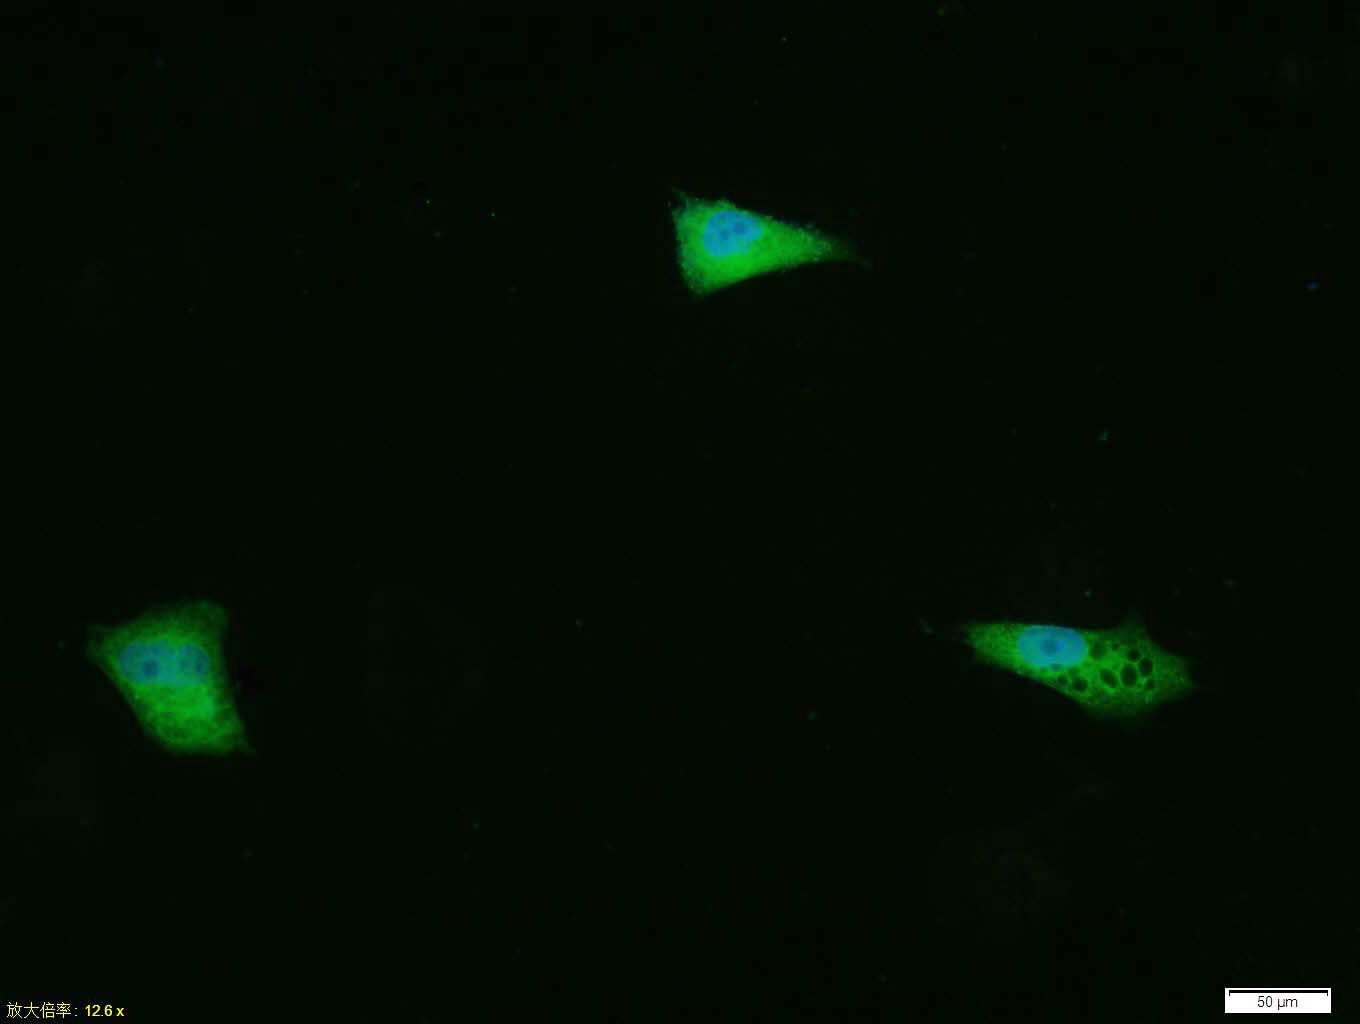

Tissue/cell: HUVEC cell; 4% Paraformaldehyde-fixed; Triton X-100 at room temperature for 20 min; Blocking buffer (normal goat serum, C-0005) at 37°C for 20 min; Antibody incubation with (phospho-ERK1/2 (Thr202 + Tyr204)) polyclonal Antibody, Unconjugated (bs-3016R) 1:100, 90 minutes at 37°C; followed by a FITC conjugated Goat Anti-Rabbit IgG antibody at 37°C for 90 minutes, DAPI (blue, C02-04002) was used to stain the cell nuclei.

Tissue/cell: Hela cell; 4% Paraformaldehyde-fixed; Triton X-100 at room temperature for 20 min; Blocking buffer (normal goat serum, C-0005) at 37°C for 20 min; Antibody incubation with (phospho-ERK1/2 (Thr202 + Tyr204)) polyclonal Antibody, Unconjugated (bs-3016R) 1:100, 90 minutes at 37°C; followed by a FITC conjugated Goat Anti-Rabbit IgG antibody at 37°C for 90 minutes, DAPI (blue, C02-04002) was used to stain the cell nuclei.